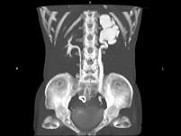

- 多项选择题女,42岁, 左侧腰背部胀痛不适1年余,5年前行左侧卵巢囊肿切除术, CT检查如图所示,下列说法正确的是 ( )

A、左侧附件区可见一囊性肿物,压迫输尿管下段

B、左侧输尿管下端狭窄

C、左侧肾盂肾盏扩张积水

D、左侧输尿管中上段扩张

E、考虑为左侧卵巢囊肿术后复发压迫并粘连输尿管致其狭窄